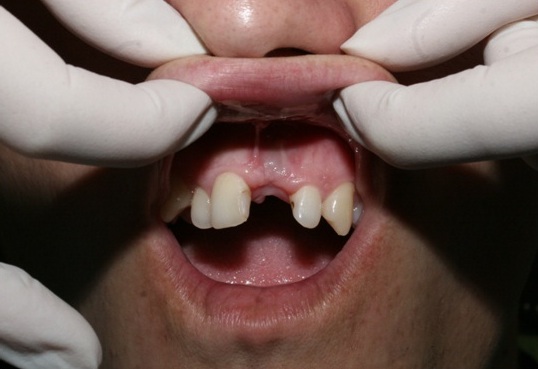

The examination found a sinus tract with an active inflammatory symptomatology. The endodontic treatment failed to give any positive results. There was made a decision to extirpate the 21st tooth along with simultaneous placement of Alpha Dent Implant with its diameter of 5 mm, 13 mm long and closure of soft tissue defects with PRP membrane. The surgery was carried out without immobilization of mucosa-periosteal graft making it possible to attain a good aesthetic look of the gingival edge and harmonious “rose-and-white” ratio.

A temporary gum shield was made for the patient to wear during the period of rehabilitation on his maxilla both for the aesthetic look and preservation of his interdental papillae. The positive result was obtained due to use of blood potential effective for soft tissue regeneration.

The surgery of an implant opening without a vestibule-oral graft throwing away was carried out in six months after the surgical stage. Availability of a sufficient amount of soft tissues in the region of implant placement made it possible to give up the usage of zirconium abutments and make use of a standard anatomic abutment to obtain positive clinical result.